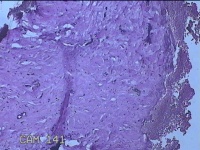

性别

女

年龄

27岁

临床诊断

乳腺脓肿

一般病史

发现右侧乳腺脓肿1个月余,伴局部疼痛不适。

标本名称

右侧乳头下方结节

大体所见

灰白暗红色结节0.8x0.5x0.3cm一个,表面糜烂。

图4

组织没固定好